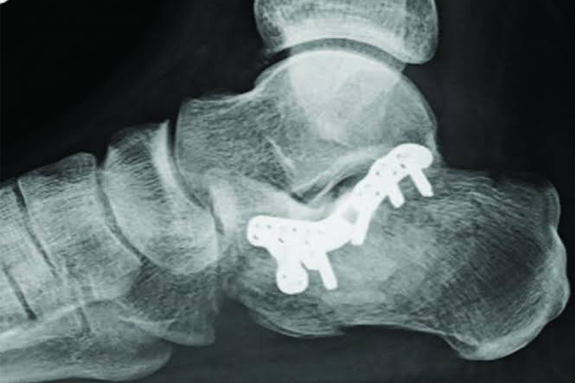

- Arthroplasty

Fracture Treatment

Hip Replacement

Trauma Surgery